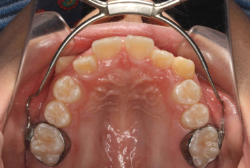

成長発育期の上顎前突症例・非抜歯治療

診断の結果、典型的なアングル2級1類の上顎前突です。上下歯列の正中の不一致も見られます。しかし、歯の大きさは平均値に近く、配列の凸凹がそれほど見られません。このまま放置すると、将来的には抜歯を伴う矯正治療を行う可能性が高くなりますが、このタイミングで適切な治療をすると、非抜歯治療が可能かもしれません。

矯正歯科医が着目するのは、奥歯の噛み合わせの位置関係です。前歯の位置にそれなりの差が生じていても、奥歯の位置が正しければそれほど重症という評価にはなりません。このケースの場合は、上下の第一大臼歯の位置関係は、直線的に一致しているタイプでした(矢印が一致)。混合歯列時期の奥歯の位置関係としては、ほぼ正常な状態といえますが、症状から言うと、上の奥歯をもっと後ろに下げてやることができれば、上顎歯列全体に余裕ができるので、凸凹も解消できるし、前歯の傾きを内向きに修正することもできると考えられました。しかしこのまま全体に永久歯が生えきってしまうと、上の前歯が出たままになってしまいますので、生え替わりが完了する前に大急ぎで奥歯を後ろに下げる必要があると判断しました。

こういう症状でもっとも効果があるのが、顎外固定装置と言って、お口の外部から奥歯に力をかける方法です。 写真の装置はネックバンドというタイプの装置です。この装置は取り外し式ですので、夜寝るときに毎日自分で取り付けて、寝ている間に少しずつ上の奥歯を後ろに下げていきます。この装置には、奥歯を後ろに下げる効果だけでなく、上顎の過剰な成長発育の抑制、下顎の成長促進作用があるとされており、上顎前突の症状にはいずれも有利な効果が期待できます。

ネックバンドを1年半使用して、上顎大臼歯が十分後ろに下がったところで、裏側にリンガルアーチという固定のワイヤーを取り付けて、新しく生じた隙間が狭くならないよう「保隙(ほげき)」という処置をして、永久歯が生えそろうまで待機中の様子です。配列全体に隙間が生じているのがお分かりいただけると思います。これだけの隙間が確保できていれば、抜歯をしなくても、あとで上の前歯を内側に理想的な角度で引っ込めることができます。このように完全に永久歯列になる前に、十分な隙間が確保できるかどうかが、非抜歯で矯正できるかどうかの分かれ目になります。

初診時と違い、上の奥歯がより後方に下がっていることが分かります。ただしこの段階では奥歯は後ろに下がりすぎの状態です。しかし次の段階でマルチブラケット法を始めると、上の奥歯は次第に前にズレて来ます。最終段階で正しい位置にするためには、この段階では余分に後ろに下がっている必要があります。

第2段階としてマルチブラケット法を非抜歯で1年間行いました。歯の傾斜が修正され、正中も一致し、美しく機能的な配列に仕上がりました。再診時に確保した隙間をすべて使って、すべての永久歯を理想的な位置に配列することができました。前傾していた上の前歯は真っ直ぐに直立し、完全な正常咬合が確立できています。